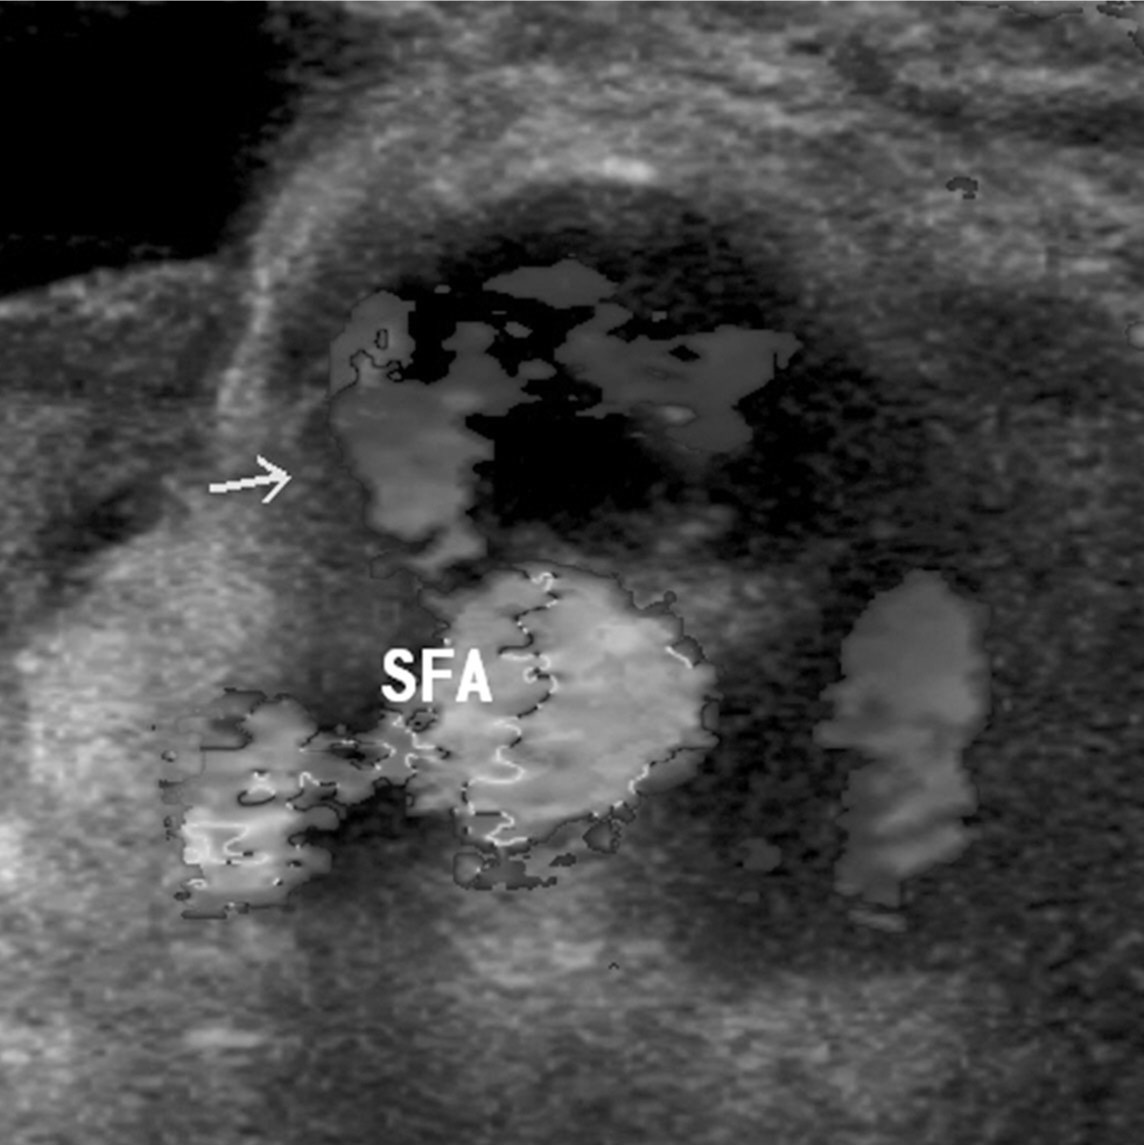

Fig. 4. A

Fig. 4A, B. On Doppler US (A) immediately after thrombin injection, there is no color swirl, indicating disappearance of pseudoaneurysm. On CT scan (B) obtained two days after thrombin injection, there is no visible pseudoaneurysm.